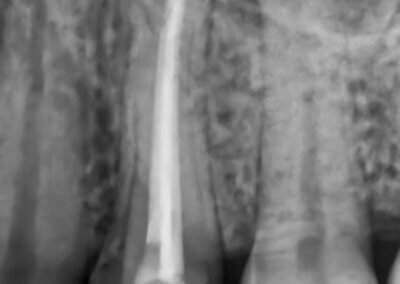

Endodonția este o ramură esențială a stomatologiei, axată pe diagnosticarea, prevenirea și tratamentul afecțiunilor pulpei dentare și a țesuturilor periapicale. Această specialitate joacă un rol crucial în salvarea dinților naturali, evitând extracțiile și menținând sănătatea orală pe termen lung. Prin tehnici avansate și echipamente de ultimă generație, endodonția asigură tratamente precise și eficiente, contribuind la redarea sănătății și funcționalității dinților într-un mod durabil și predictibil.

Utilizarea tehnicilor moderne asigură un tratament rapid, precis și confortabil pentru pacient.

Reconstituirea coronară cu materiale de calitate conferă rezistență pe termen lung.